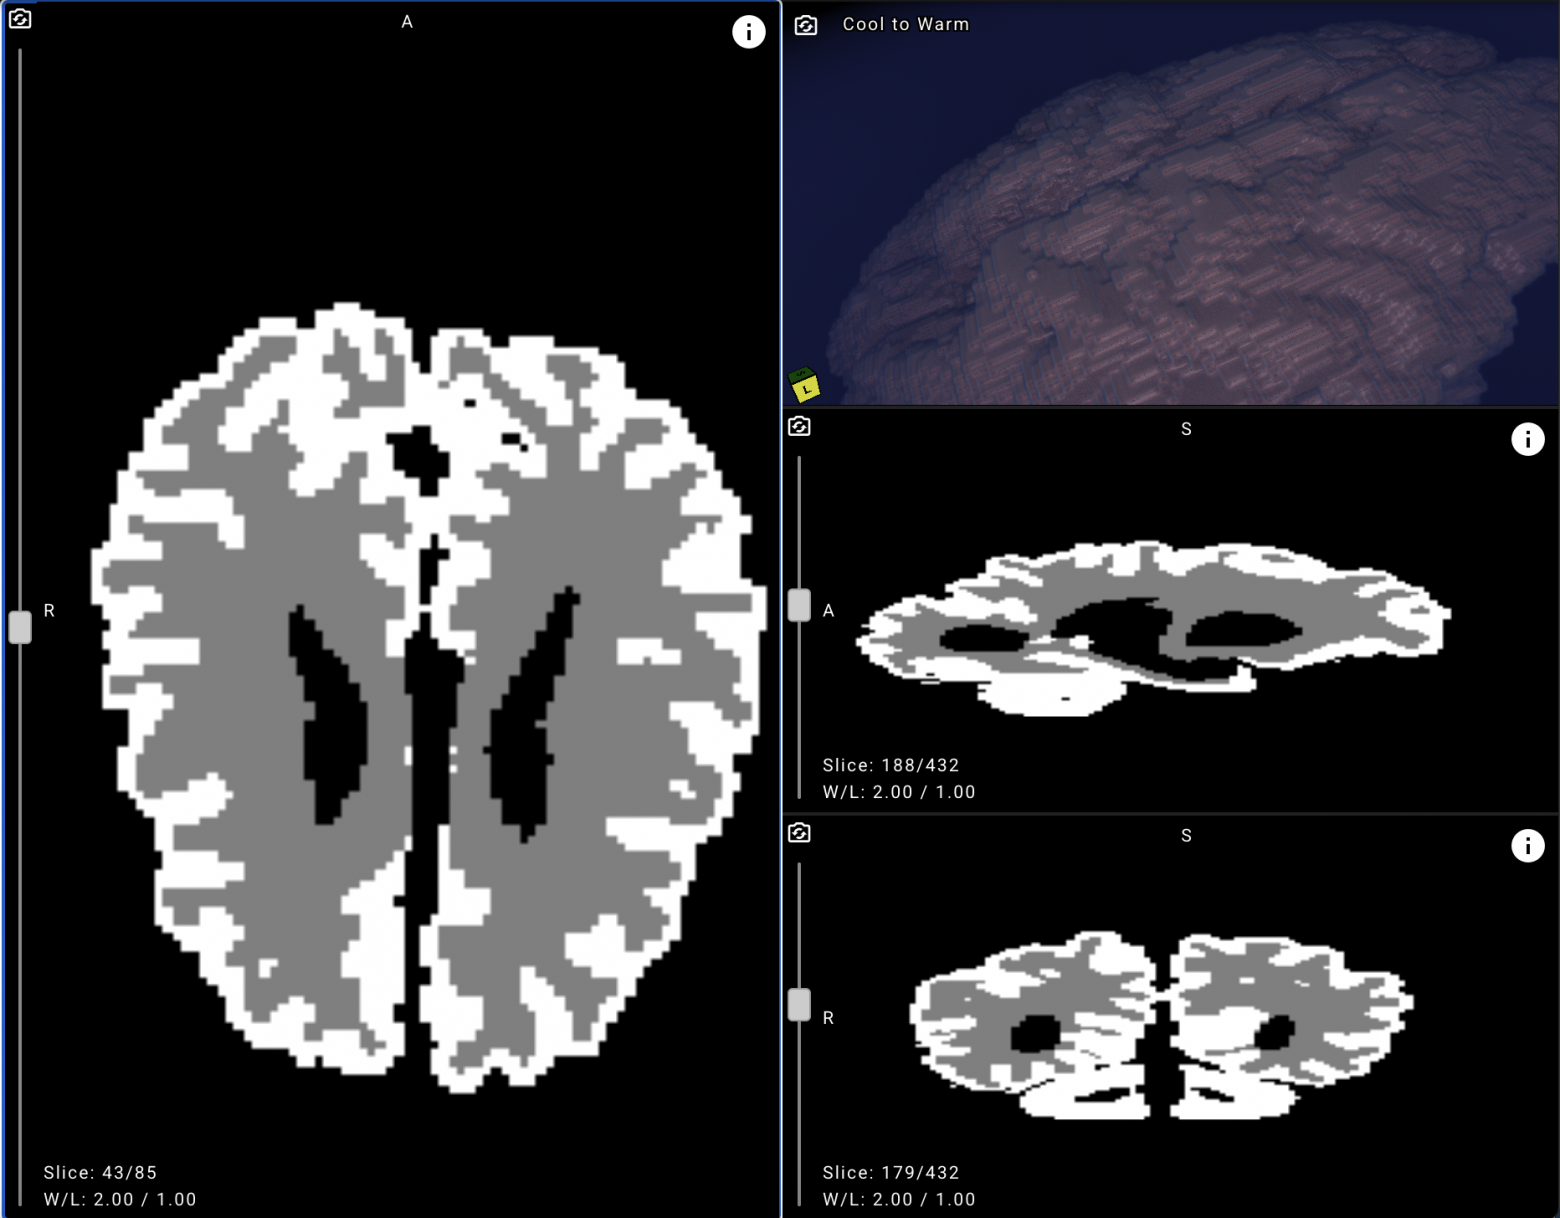

Решение автоматически определяет на каждом срезе МРТ, где находится серое и белое вещество, с определённой долей вероятности.

Сервис в первую очередь морфометрический, измеряющий объёмы. После обработки пользователь видит предсказанный моделью объём серого и белого вещества и цереброспинальной жидкости (ЦСЖ), а также описание крупнейших структур.

Из таблицы можно перейти в само исследование, где уже выделены маски белого и серого вещества:

По результатам экспериментов, точность составляет выше 90% — эта цифра может меняться по мере увеличения количества данных и дообучения решения, так как решение обучалось на ограниченном датасете.